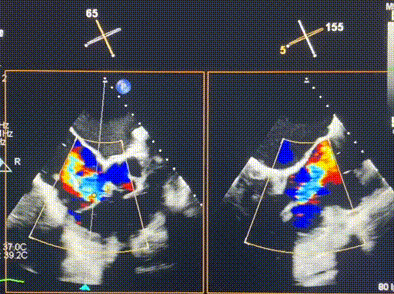

術(shù)前超聲提示重度三尖瓣反流

接受本次LuX-Valve Plus治療的是一位三尖瓣重度反流的高齡女性,患者早前曾由于二尖瓣疾病行經(jīng)導(dǎo)管二尖瓣置換術(shù),植入Tendyne瓣膜一枚,且有ICD植入史。術(shù)前CT分析結(jié)果顯示,瓣環(huán)大小為47.6mm,血管無明顯迂曲和鈣化。由于患者三尖瓣解剖結(jié)構(gòu)復(fù)雜,二尖瓣位人工瓣膜造成的超聲偽影和ICD導(dǎo)線的干擾使得歐洲沒有其他合適的商業(yè)化和臨床試驗的產(chǎn)品可以對其進(jìn)行治療。經(jīng)過Rodrigo Estévez-Loureiro教授團(tuán)隊的詳盡術(shù)前評估,認(rèn)為LuX-Valve Plus經(jīng)導(dǎo)管三尖瓣置換系統(tǒng)可以對該患者進(jìn)行有效的治療。因此,Rodrigo Estévez-Loureiro教授團(tuán)隊最終決定使用這一中國創(chuàng)新器械為患者進(jìn)行手術(shù)。法國波爾多里爾大學(xué)附屬醫(yī)院的Thomas Modine教授與加拿大圣保羅醫(yī)院的Anson Cheung教授全程線下指導(dǎo)本次手術(shù)。